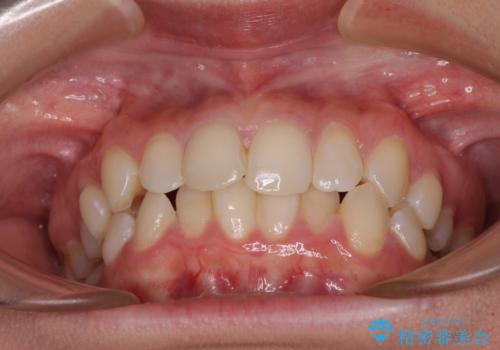

- 前歯のデコボコと歯肉に埋もれている奥歯を気にして来院された患者様です。

インビザラインでの治療を希望されていましたが、左右の下顎大臼歯が歯肉に埋もれており、特に右側は歯軸が顕著に傾斜していたため、インビザライン単独での治療は困難と判断し、ワイヤー装置を併用することとしました。

ワイヤー装置での下顎臼歯改善には時間がかかることが予想されたため、下顎のワイヤー矯正と並行して上顎をインビザラインで整え、その後インビザラインにより上下歯列を整える矯正治療を行うこととしました。

ワイヤー装置を併用したことで、レントゲン写真からも分かるとおり歯軸をしっかりと改善させることができました。